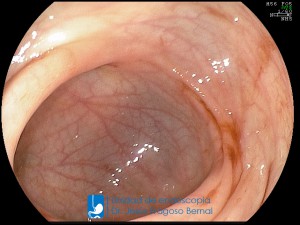

La Unidad de Endoscopía fue creada en 2002 por el Dr. Jesús Fragoso Bernal, es pionera en el estado por la utilización de la tecnología más avanzada, que nos permite ofrecer servicios integrales de diagnóstico y tratamiento para las enfermedades del aparato digestivo.

El profesionalismo de nuestro personal, altamente especializado, se distingue por la calidad y calidez de nuestros servicios con el objetivo de brindar una atención de excelencia en el ambiente más confortable para comodidad y seguridad de nuestros pacientes.

"La Unidad de Endoscopía se ha caracterizado por un progreso continuo desde su inicio marcando la pauta en los procedimientos endoscópicos en el estado de Tlaxcala y estando siempre a la vanguardia tecnológica."

Dr. Jesús Fragoso Bernal